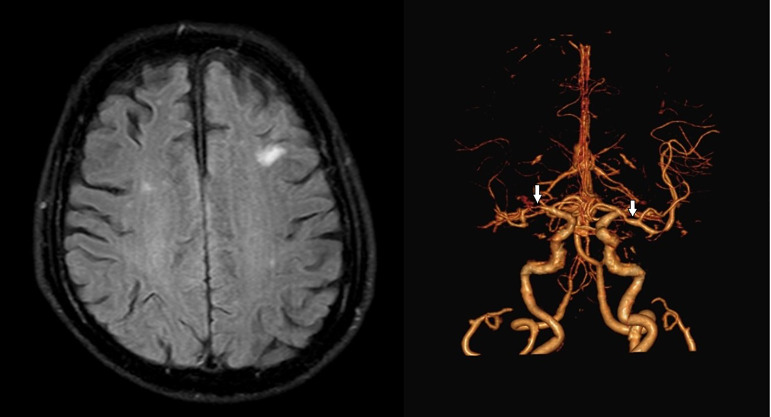

Results: Among 234 acute NCIS cases, 113 exhibited ICAS, 12 had ECAS, 20 had both, and 89 had neither. The RNF213 rs112735431 gene variant was detected in 2 patients, both heterozygous A/G. The frequency of the RNF213 rs112735431 variant was 0.9% (2/234; 95% CI: 0-2.1%) in acute NCIS patients and 1.8% (2/113; 95% CI: 0-4.2%) in ICAS. All individuals with the RNF213 variant were males with hypertension, diabetes mellitus, dyslipidemia, and ICAS, without a family history of ischemic stroke.

Abstract Image